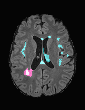

In recent years, data-driven machine learning (ML) methods have revolutionized the computer vision community by providing novel efficient solutions to many unsolved (medical) image analysis problems. However, due to the increasing privacy concerns and data fragmentation on many different sites, existing medical data are not fully utilized, thus limiting the potential of ML. Federated learning (FL) enables multiple parties to collaboratively train a ML model without exchanging local data. However, data heterogeneity (non-IID) among the distributed clients is yet a challenge. To this end, we propose a novel federated method, denoted Federated Disentanglement (FedDis), to disentangle the parameter space into shape and appearance, and only share the shape parameter with the clients. FedDis is based on the assumption that the anatomical structure in brain MRI images is similar across multiple institutions, and sharing the shape knowledge would be beneficial in anomaly detection. In this paper, we leverage healthy brain scans of 623 subjects from multiple sites with real data (OASIS, ADNI) in a privacy-preserving fashion to learn a model of normal anatomy, that allows to segment abnormal structures. We demonstrate a superior performance of FedDis on real pathological databases containing 109 subjects; two publicly available MS Lesions (MSLUB, MSISBI), and an in-house database with MS and Glioblastoma (MSI and GBI). FedDis achieved an average dice performance of 0.38, outperforming the state-of-the-art (SOTA) auto-encoder by 42% and the SOTA federated method by 11%. Further, we illustrate that FedDis learns a shape embedding that is orthogonal to the appearance and consistent under different intensity augmentations.